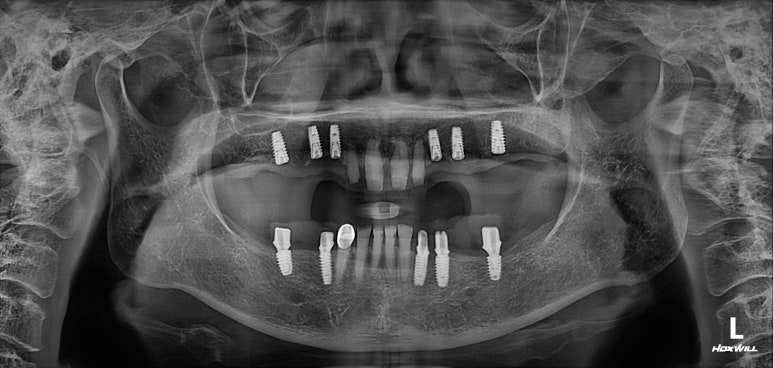

엑스레이는 지난 내원 때 찍었던 것인데, 한가지 알 수 있는 것은?

다행히도 잇몸뼈가 건강하고 많아서 충분히 임플란트로 치료가 가능하다는 것!!

보시면 아래턱뼈에 총 5개의 임플란트를 심어드렸습니다.

사실 7개의 임플란트를 심어드려야 아래턱 치아 총 14개를 만들어드릴 수 있습니다만,

위턱에 뼈이식을 하면서 임플란트 1차 수술을 먼저 시행했습니다.

왼쪽 3개 오른쪽 3개 총 6개의 임플란트를 뼈이식과 함께 수술해드렸어요.

엑스레이 또한 빼놓을 수 없죠!!

적절한 위치에 심어진 임플란트는 곧 적절한 임플란트 크라운으로 이어지게 되고,

당연히 모양도 예쁘게 제작되겠지만, 음식물이 끼는 것도 최소화됩니다.